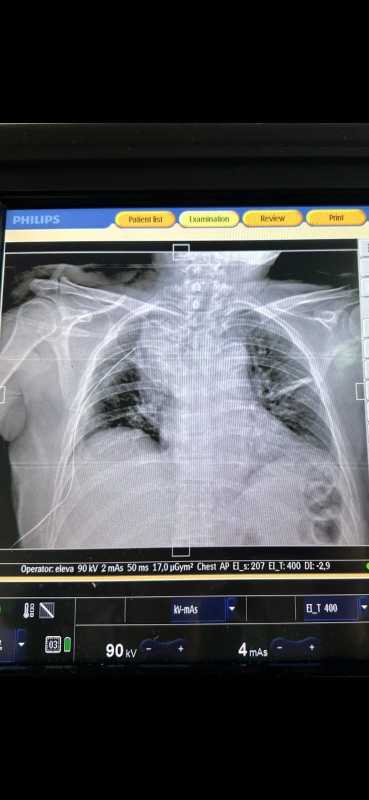

În chirurgia toracică, Inteligența Artificială oferă beneficii prin îmbunătățirea acurateței diagnosticării și a planificării, asistarea în timpul operațiilor pentru o mai mare precizie și reducerea riscurilor și prin eficientizarea proceselor postoperatorii. IA ajută la prelucrarea imaginilor medicale pentru detectarea timpurie a bolilor și la personalizarea strategiilor chirurgicale, oferind suport în luarea deciziilor clinice. Ea poate analiza rapid și precis imagini medicale (cum ar fi radiografii, CT-uri) pentru a detecta anomalii, a ajuta la diagnosticarea bolilor pulmonare și a stadiilor cancerului pulmonar și a planifica intervenția chirurgicală în detaliu.

Deși nu apelează la IA, chirurgul subliniază că pacienții pot beneficia de multiple metode de diagnostic în cadrul spitalului, implicit al Compartimentului de Chirurgie Toracică, de la consulturi interdisciplinare (consult cardiologic, anestezie, neurologie, diabet) necesare în pregătirea preoperatorie până la analize de laborator, imagistică (radiografii, tomografii, RMN, Pet-CT). AGERPRES/(AS - redactor: Otilia Halunga, editor: Karina Olteanu, editor online: Andreea Lăzăroiu)